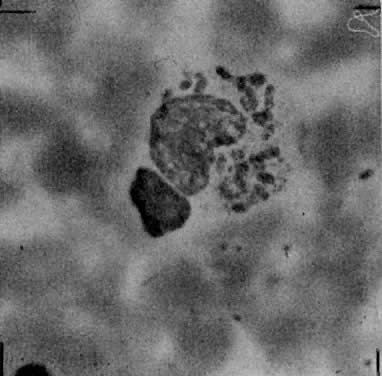

Both LGV and non-LGV strains of chlamydia may be grown in McCoy cells, a heterophile mouse cell-culture line. These cells are first inhibited by irradiation or with 5-iodo-2-deoxyuridine, permitting the chlamydia to more easily compete for cell nutrients. This allows easier recognition of intracytoplasmic inclusions after staining with iodine (Fig. 1).5

Fig. 1. Intracytoplasmic inclusion of chlamydia on McCoy cell monolayers after staining with iodine (original magnification × 90)